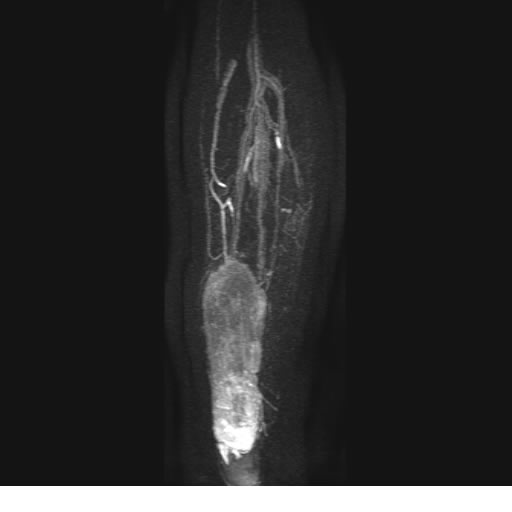

Se realiza estudio de MRI de pierna izquierda, utilizando secuencias Spin Echo y GRE en diferentes planos, se realiza angio MRI en fase arterial y venosa de pierna izquierda

El estudio demuestra masa a nivel de los músculos gemelos, más evidente en secuencia con pulso de saturación de grasa, en el estudio de angio resonancia de pierna la fase arterial no muestra ninguna anormalidad, en la fase venosa se observa acumulo del medio de contraste a este nivel.

Se concluye que se observa una masa de tejido muscular sumamente vascularizada compatible con un hemangioarcoma.